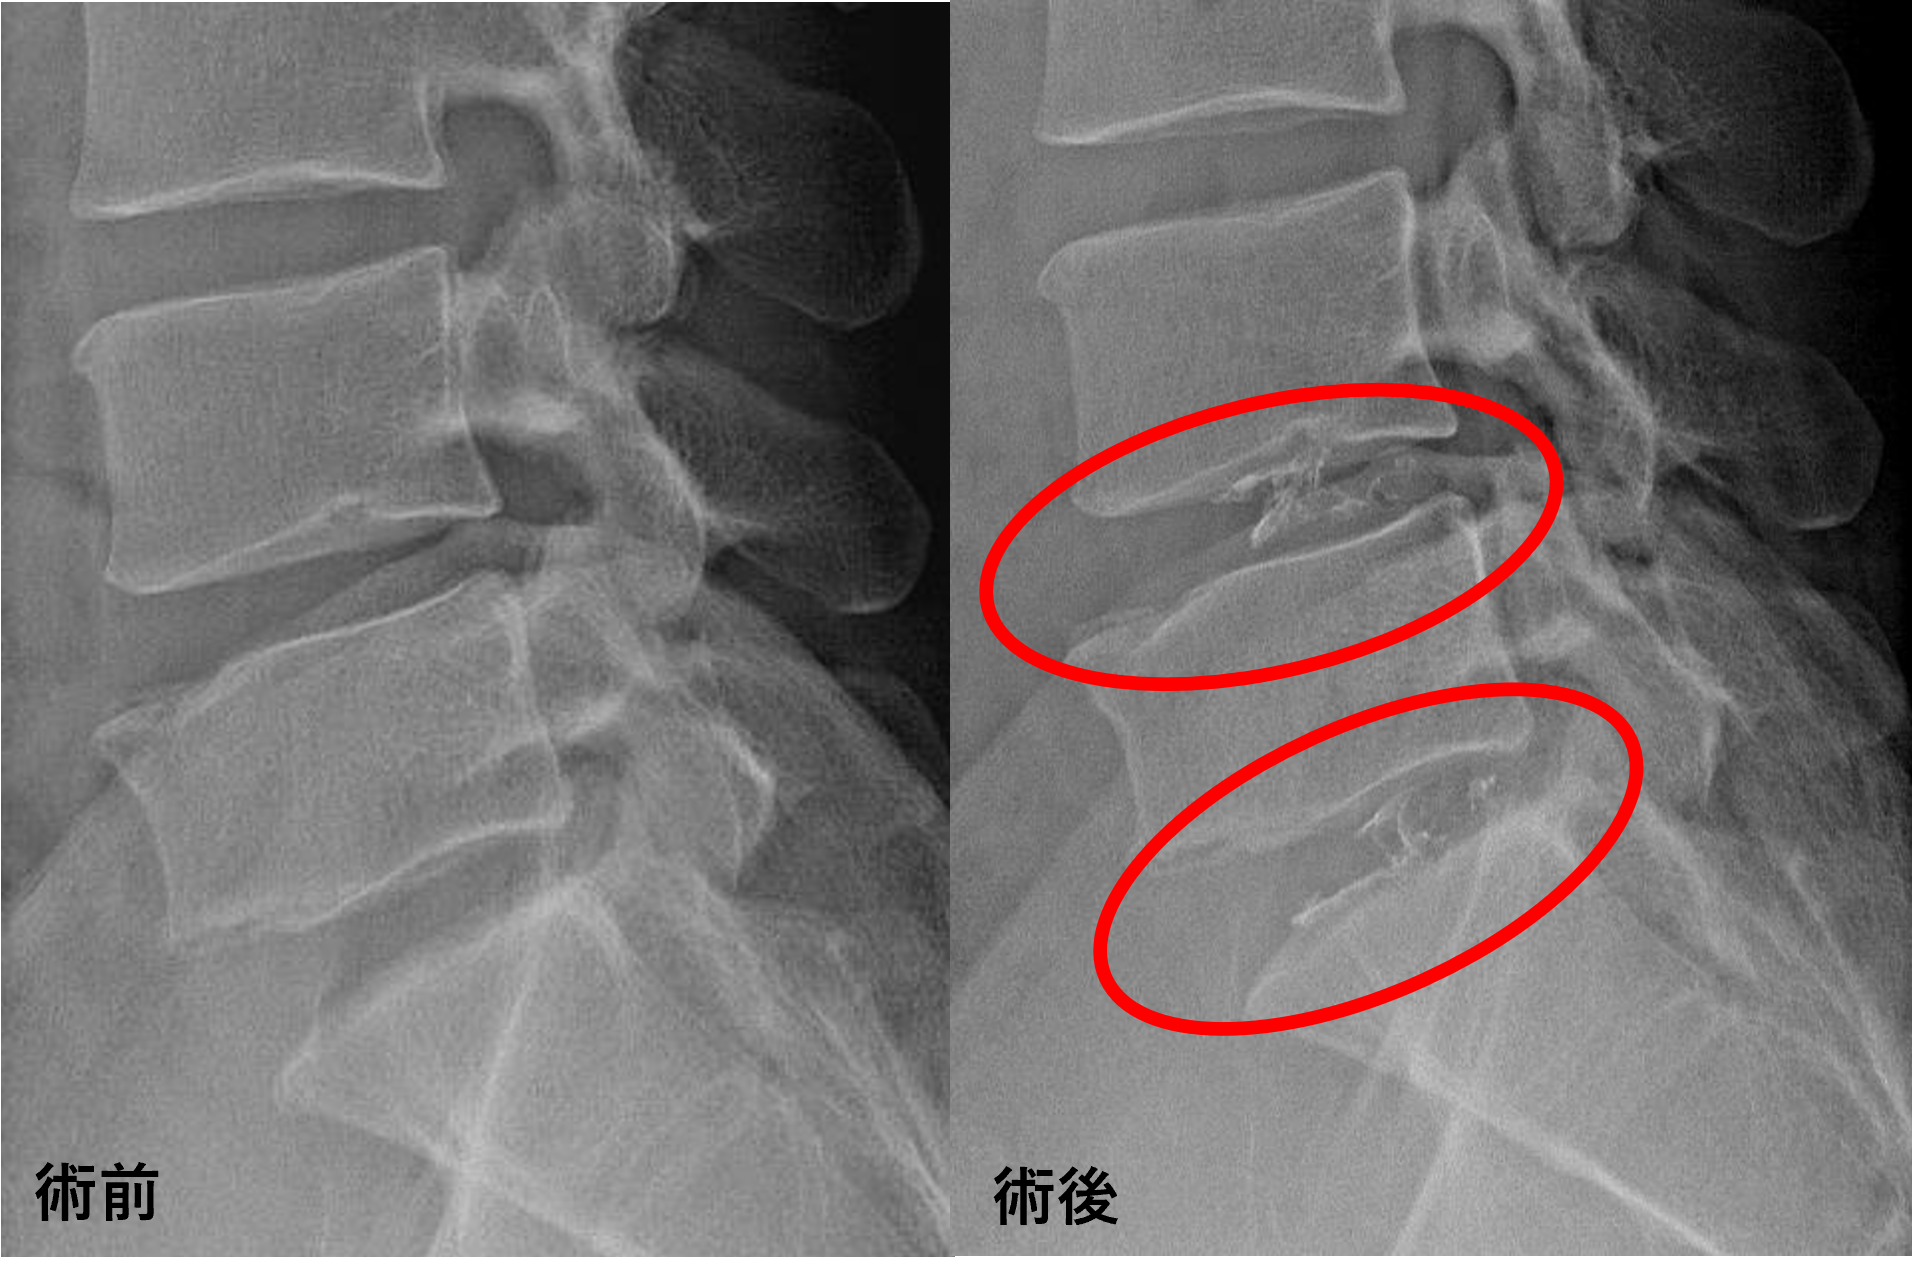

画像及び所見について

- L4/5、5/s – 椎間板変性、椎間板ヘルニア

以上のことが画像上認められました。

L4/5、5/sの椎間板所見による脊柱管の圧排が、症状の原因の可能性が高い。

患者様と相談の元、L4/5、5/sにセルゲル法を施行